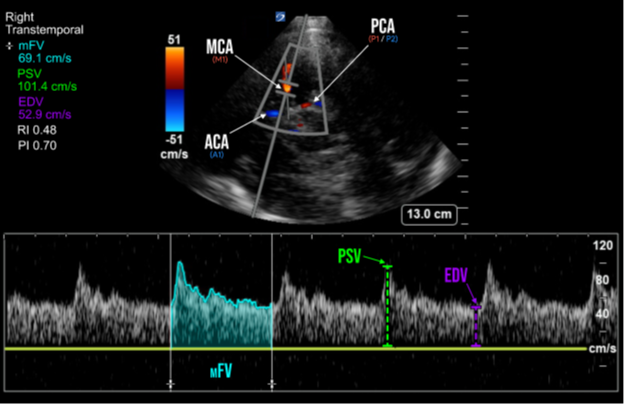

The transducer indicator should point towards the ipsilateral eye in the TCD pre-set, or towards the occiput if in Cardiac pre-set (Figure 1). The transducer is then oriented slightly upwards and anteriorly. Key landmarks of the transtemporal window include the hypoechoic, butterfly-shaped, cerebral peduncles, and are surrounded by the echogenic, star-shaped, basal cisterns. Color Doppler is then applied over this area and should reveal the circle of Willis. Multiple segments of the intracerebral vessels are able to be visualized in the transtemporal window, including those of the middle cerebral arteries (MCA), anterior cerebral arteries (ACA), and posterior cerebral arteries (PCA) (Figure 1 & 2). Pulsed-Wave Doppler is then applied with the gate placed through the ipsilateral MCA, which appears as a red color doppler signal traveling towards the probe. The normal spectral waveform of the MCA includes the following characteristics: a sharp systolic upstroke and a stepwise diastolic deceleration with positive end-diastolic flow. (Figure 2)

The primary parameter of TCD is known as the Mean Flow Velocity (mFV) (which is also called Time Average Mean, or TAM). MCA Vasospasm is defined by a mFV >120 cm/s, with severity further categorized as mild (>120 cm/s), moderate (>150 cm/s), and severe (>200 cm/s).1,3 mFV is calculated through measurement of the Peak-Systolic Velocity (PSV) and End-Diastolic Velocity (EDV) on spectral doppler, however some ultrasound machines are capable of automatic calculation of the mFV by tracing of the spectral doppler waveform (Figure 2).

Figure 2. Spectral doppler of the middle cerebral artery (MCA) and its measured parameters In addition to vasospasm, other pathologies causing cerebral hyperemia from global hyperdynamic blood flow (sepsis, fever, anemia, hypercapnia, etc.) can also increase MCA mFV. Further differentiation can be accomplished through calculation of the Lindegaard ratio, which is simply a ratio of the MCA mFV divided by the ipsilateral extracranial internal carotid artery (ICA) mFV. The Lindegaard ratio can thus not only help with differentiation between hyperemia and vasospasm, but is also another method of quantifying vasospasm severity.